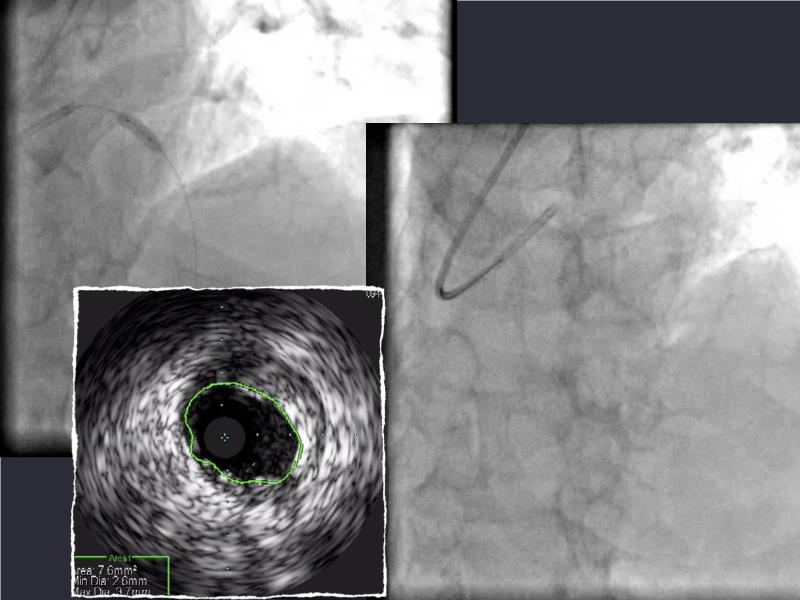

This session is a valuable resource for grasping innovative strategies in handling bifurcation and extended diffuse lesions through dedicated stenting solutions. Explore insights into the advanced Myval next-generation THV technology, unveiling its distinctive features, procedural advantages, and clinical outcomes across a diverse patient pool. Gain understanding into the CorAlign technique, ensuring accurate commissural and coronary alignment while maintaining coronary access. Additionally, delve into the techniques for precise sizing, positioning, and deploying of Myval THV.

- To understand novel tools and techniques for effective management of bifurcation lesions and long diffused lesions using dedicated stenting solutions